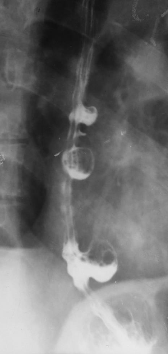

Diverticuli medioesofagieni